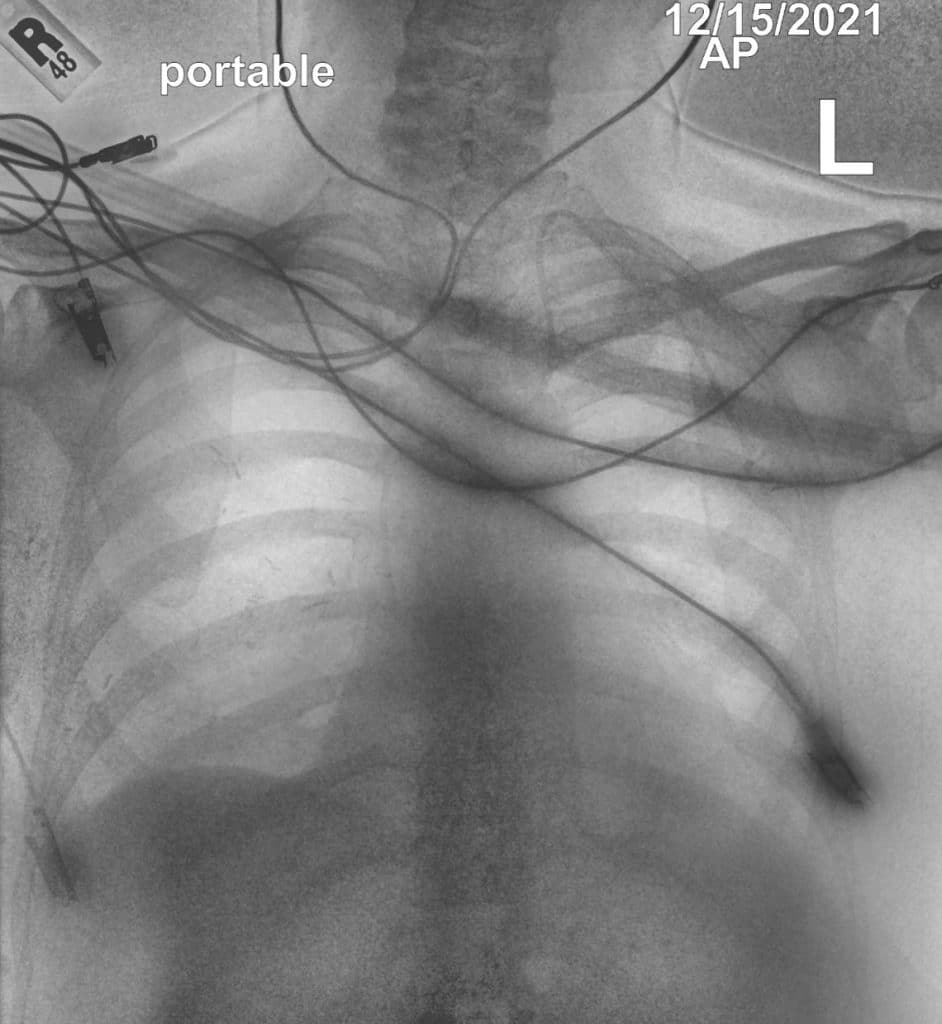

device placement following emergency procedures

visibility of lines and tube tips without extra reading times⁵

In this case, the conventional DR image shows subtle findings. The spectral soft-tissue image reduces overlying bone, making the pneumothorax more conspicuous. The corresponding bone-selective image highlights a rib fracture, a potential underlying cause of the pneumothorax.